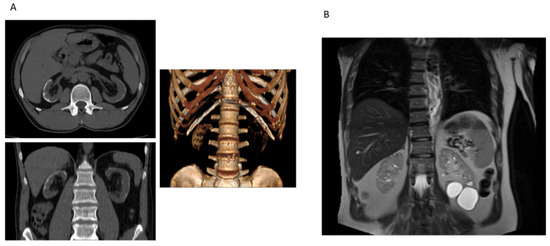

- Sevillano, A.M.; Gutierrez, E.; Morales, E.; Hernandez, E.; Molina, M.; Gonzalez, E.; Praga, M. Multiple Kidney Cysts in Thin Basement Membrane Disease with Proteinuria and Kidney Function Impairment. Clin. Kidney J. 2014, 7, 251–256. [Google Scholar] [CrossRef]

- Gulati, A.; Sevillano, A.M.; Praga, M.; Gutierrez, E.; Alba, I.; Dahl, N.K.; Besse, W.; Choi, J.; Somlo, S. Collagen IV Gene Mutations in Adults with Bilateral Renal Cysts and CKD. Kidney Int. Rep. 2020, 5, 103–108. [Google Scholar] [CrossRef]